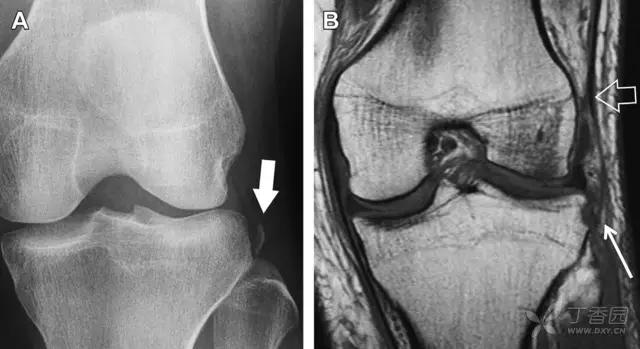

(2)反向 Segond 骨折

胫骨平台内侧皮质骨撕脱性骨折,被称为内侧 Segond 骨折或反向 Segond 骨折。这种骨折的旋转机制与 Segond 骨折相反,该骨折与后交叉韧带断裂及内侧半月板损伤相关。

一位足球运动员的反向 Segond 骨折。A 正位片示关节线处的胫骨内侧见一细小骨折片(箭头)。B MRI 冠状位 T1 加权像示骨折片出现在内侧副韧带关节囊附着处(方框)(来源:Radiol Clin N Am 53 (2015) 737–755,YU,Ohio)